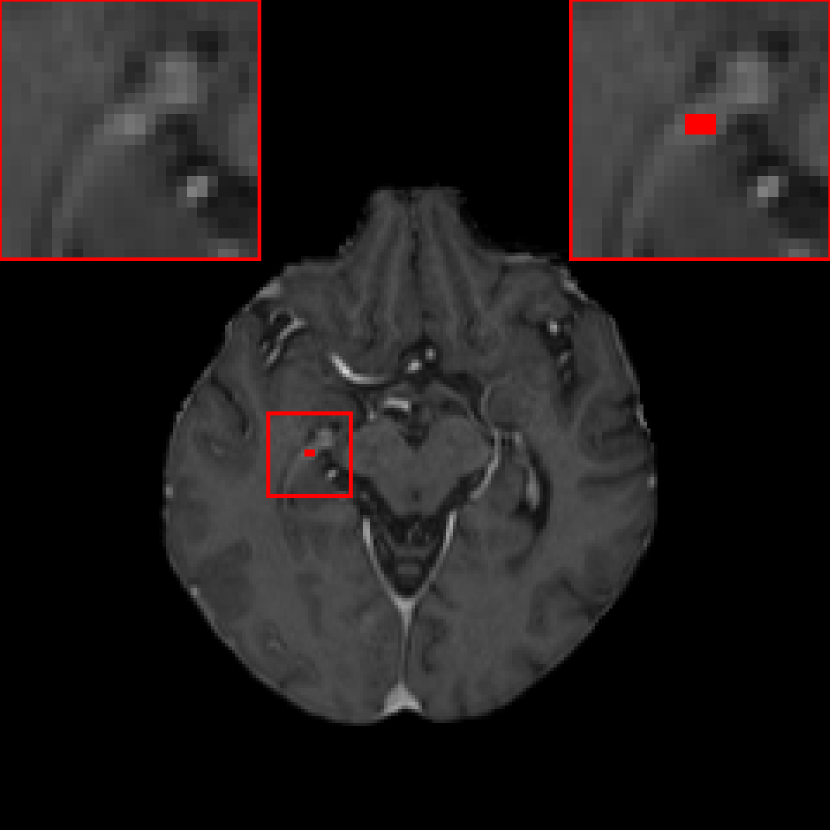

When α𝛼\alpha is decreased in the JVSS loss, the sensitivity is decreased, but the precision is improved. When α=0.9𝛼0.9\alpha=0.9, the sensitivity of DeepMedic with the JVSS loss is comparable to that of DeepMedic with BCE only. However, the precision is increased from 0.691 (237/(237 + 106)) to 0.930 (239/(239 + 18)). When α=0.5𝛼0.5\alpha=0.5, DeepMedic achieves a high precision of 0.987, with only 3 FP metastases remaining. The three FP metastases are displayed in Fig. 5. In Fig. 5, the green region is a TP metastasis and its boundary is segmented well. The red region in Fig. 5 is a FP metastasis, which is a connecting point of two vessels. The right vesicle in Fig. 5 has higher intensity than the surrounding tissues and it has a sphere-like structure in the 3D space. That is why it is falsely detected as a metastasis. The marked region in Fig. 5 has relatively higher intensity than the surrounding vessels. Therefore, whether it is a false or true positive metastasis is controversial, if we look at one single volume only. After checking with the follow-up scans, this region does not grow at all and hence we confirm that it is a FP metastasis.

[Uncaptioned image]

Figure 5: The three false positive metastases detected by DeepMedic with the JVSS (α=0.5𝛼0.5\alpha=0.5) loss are marked by red color. The green region in (a) is a detected true positive metastasis.

III.B. Results of DeepMedic+ using temporal prior

Fig. 5 is an example where temporal prior information is beneficial for metastasis identification. With an additional path for the prior volume, the red region in Fig. 5, as well as the other two cases in Fig. 5, is detected correctly. The sensitivity and precision for DeepMedic+ with the JVSS loss (α=0.995𝛼0.995\alpha=0.995 and α=0.5𝛼0.5\alpha=0.5) together with the temporal prior, i.e. senssubscriptsens\mathcal{M}_{\text{sens}} and specsubscriptspec\mathcal{M}_{\text{spec}} respectively, are displayed in Tab. 1. For α=0.995𝛼0.995\alpha=0.995 (senssubscriptsens\mathcal{M}_{\text{sens}}), the total number of FP metastases is reduced from 247 to 158, where 36.0%percent36.036.0\% ((247 - 158)/247) FP metastases are reduced. The average FP rate per patient is reduced from 2.40 (247/103) to 1.53 (158/103). As a trade-off, the sensitivity has a slight decrease from 0.946 (263/278) to 0.932 (259/278), with only 4 more FN metastases. Note that some of the test volumes are first scans without temporal prior volumes. If we exclude such volumes, the number of FP metastases decreases from 180 to 100 with the help of temporal prior, which is about 44.4% (180 - 100)/180 less, where 3 instead of 4 more FN metastases are observed. The average FP rate per patient is reduced from 2.54 (180/71) to 1.41 (100/71) for those with prior scans. For α=0.5𝛼0.5\alpha=0.5 (specsubscriptspec\mathcal{M}_{\text{spec}}), the sensitivity is slight worse than that of baselinesubscriptbaseline\mathcal{M}_{\text{baseline}}. However, the precision is as high as 0.996 (234/(234 + 1)) with only one FP metastasis. The FP case is displayed in Fig. 7, where the current main image together with its temporal prior and posterior images are displayed. The difference image between the main image and the temporal prior image is displayed in Fig. 7(c), where the area indicated by the arrow has larger difference. That is why specsubscriptspec\mathcal{M}_{\text{spec}} regards this region as a metastasis. However, after checking its posterior image (Fig. 7(d)), no grown metastasis exists. Therefore, we regard the detection in Fig. 7(b) as FP. But we cannot eliminate the possibility that a real metastasis has regressed at the segmented region before the posterior scan.